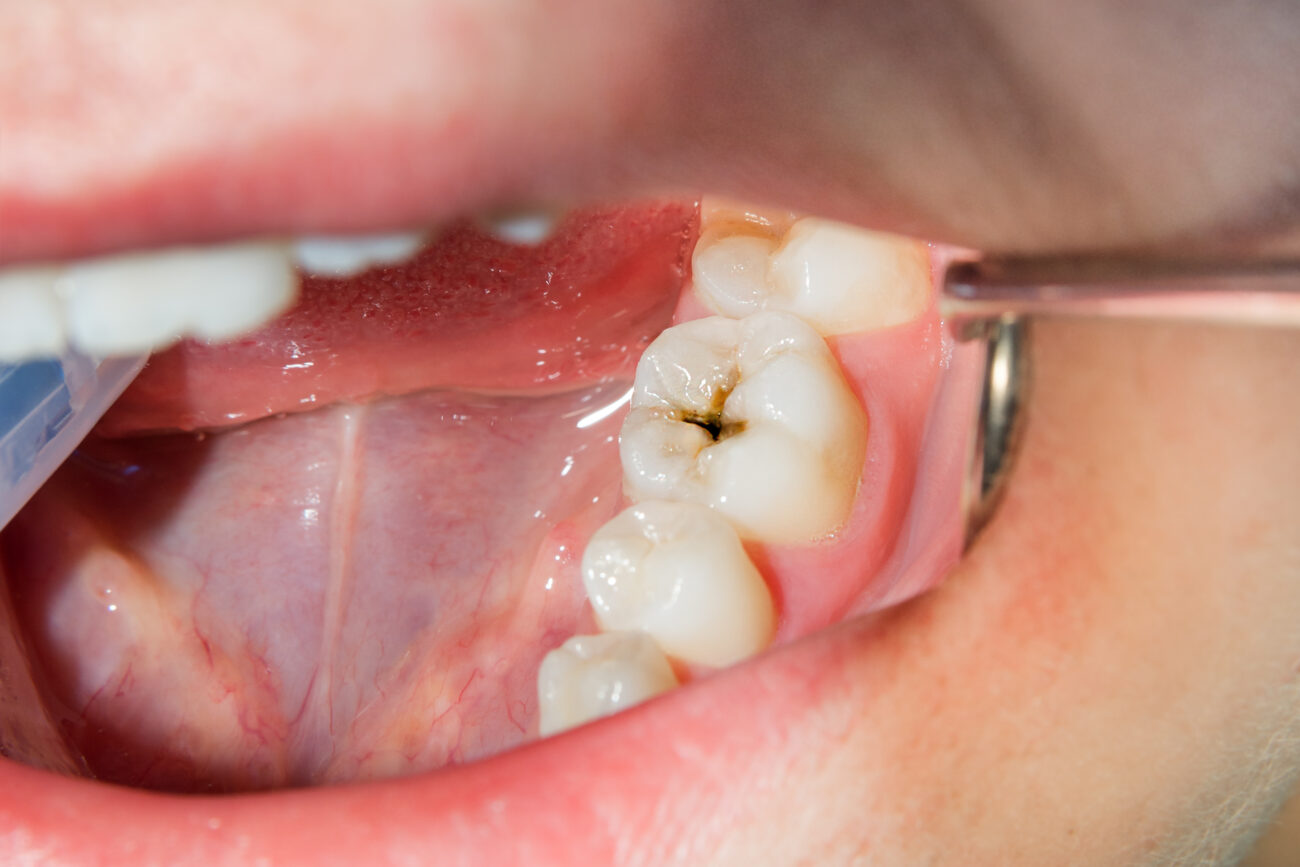

Kariesbehandlung

Karies ist die am weitesten verbreitete Erkrankung überhaupt. Nur etwa ein Prozent der erwachsenen Deutschen ist kariesfrei. Umso wichtiger ist es, Kariesbefall so früh wie möglich zu erkennen und zu behandeln. Wir empfehlen unseren Patientinnen und Patienten daher, mindestens einmal im Jahr zur prophylaktischen Vorsorgeuntersuchung zu kommen. So können kariöse Stellen frühzeitig identifiziert und beseitigt werden.

Zum Auffüllen geschädigter Zähne setzen wir auf moderne Füllungstherapien und verwenden vor allem Keramik und Composite-Kunststoff-Füllungen an. Im Vergleich zu den früher verwendeten Amalgam- oder Goldfüllungen gleichen diesen Materialien farblich viel mehr der natürlichen Zahnfärbung und sind daher weniger auffällig.